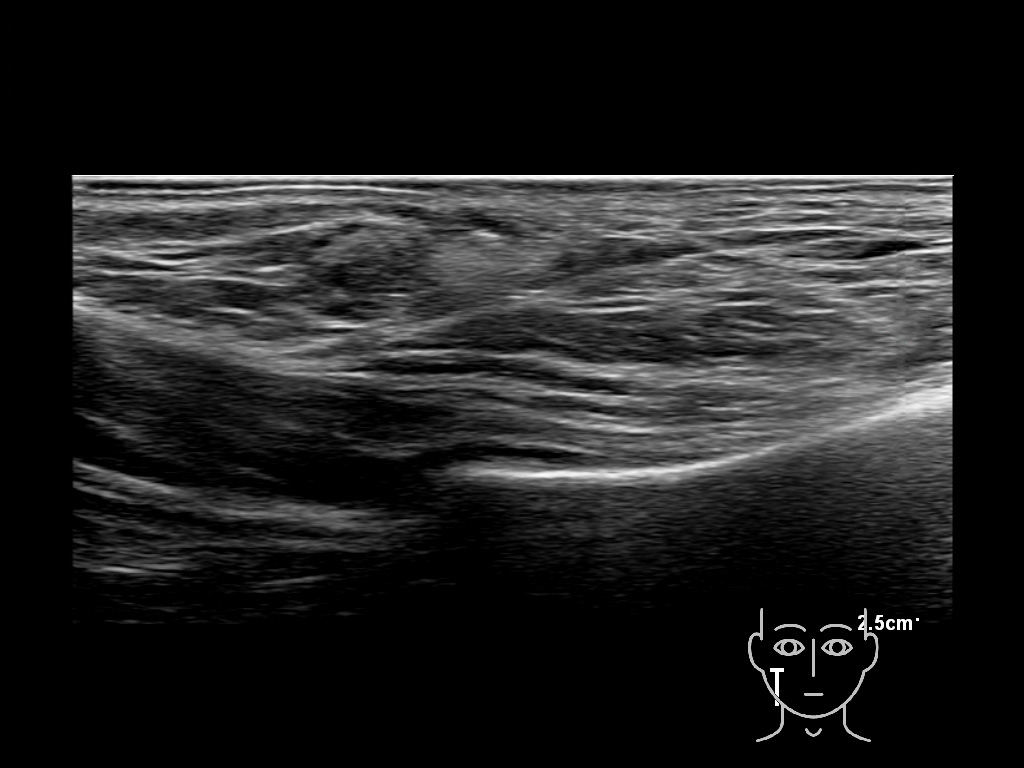

HACa 4b e